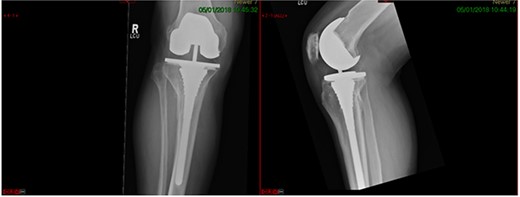

This case report follows a 67-year-old gentleman who sustained a Schatzker VI fracture of his right tibia after falling 2 m from a ladder (Fig. 6). The injury was closed and neurovascularly intact; he was managed initially in a neighbouring health board with a bridging external fixator because of the high degree of comminution. He was referred to the current institution; and at a routine review 3 weeks post-injury, it was noted that a pin had fractured. The external fixator was removed, and he was converted into an above knee cast. He progressed to a Sarmiento cast and then a range of motion brace at 12 weeks. Partial weight bearing was permitted, and he received physiotherapy. He was kept under regular review and the fracture had united (Fig. 7); he was noted to have a range of movement of 10°–60° with healed pin site wounds. At 8 months post-injury, he underwent total knee arthroplasty utilizing a posterior stabilised Depuy Synthes (Warsaw, In) Attune revision tibial metaphyseal sleeve and stem, and femoral component without sleeve or stem. The patient had an uncomplicated recovery and kept under routine review in the outpatient clinic. At 6 months’ review, the patient had a range of motion of 0°–105°, fully healed wound and reported a significant improvement in pain. The patient used no walking aids, and the Oxford Knee score was 40 (Fig. 8).